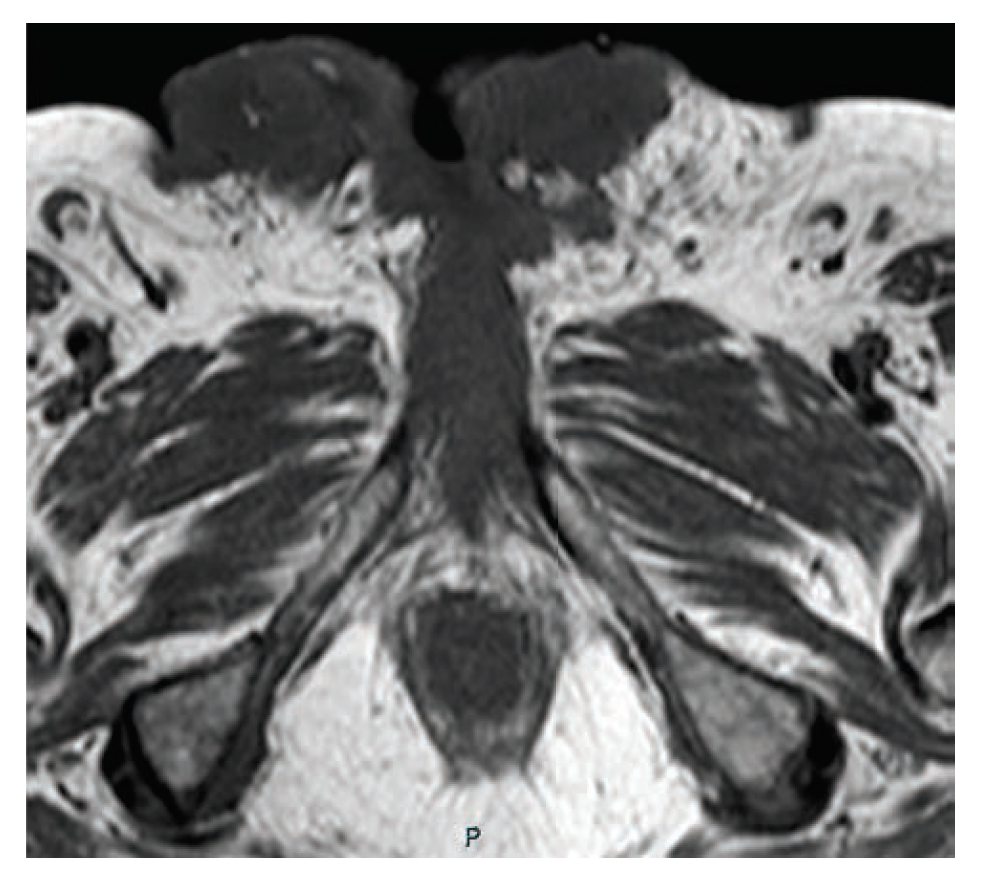

CT staging scans confirmed the primary tumor and a suspicious left 1.2-cm inguinal lymph node but no distant metastases. MRI of the pelvis revealed complete replacement of the penis with tumor as well as invasion into the scrotum and bilateral groin soft tissue; additionally, early pubic bone invasion was present, with left groin lymphadenopathy. Biopsy verified squamous cell carcinoma of the penis, and discussion with the multidisciplinary team uroradiologist confirmed bony invasion (Figure 1).

FIGURE 1. MRI of Penile Cancer Showing Early Invasion Into Bone and Destruction of Penile Anatomy